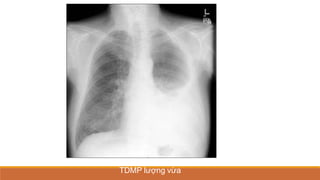

TDMP lượng ít

TDMP lượng vừa

TDMP lượng nhiều

TDMP TỰ DO

PHIM THẲNG ĐỨNG

•TÙ GÓC SƯỜN HOÀNH

•BÓNG MỜ VÙNG THẤP XÓA BỜ VÒM HOÀNH VỚI

GIỚI HẠN TRÊN LÀ ĐƯỜNG CONG DAMOISEAU

•ĐẨY TRUNG THẤT VỀ PHÍA ĐỐIDIỆN

•XẸP PHỔI THỤ ĐỘNG (+/-)

•THAY ĐỔI THEO TƯ THẾ